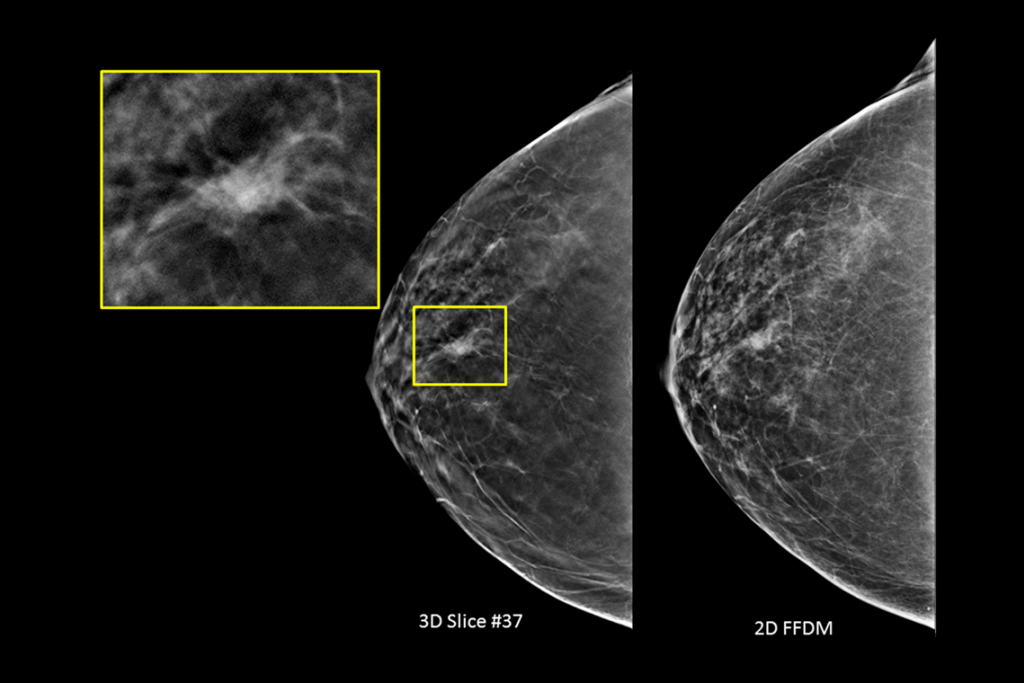

Clinical images of breast scan mammography

Clinical images of breast scan with suspicious Lesion

Clinical images of breast scan

Clinical images of breast scan with fatty breast